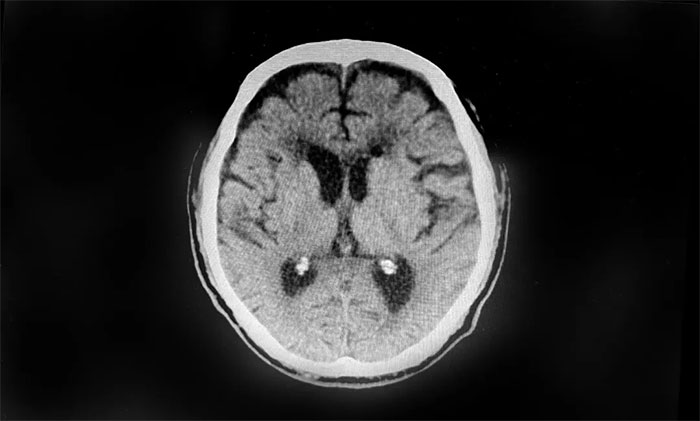

▲ 术后复查,血肿得到明显改善

待病情稳定并评估后,近期,于耀宇主任又为患者开展了双侧“硬脑膜下钻孔引流术”,促使硬膜下积存的大量血肿快速排出,解除脑组织压迫,缓解头晕、肢体乏力等症状。术后,患者健康状况平稳,病情正逐渐好转。